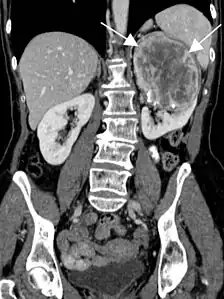

- Tumeur fibreuse solitaire du rein

Aspect tomodensitométrique. La tumeur est repérée par les flèches[46].